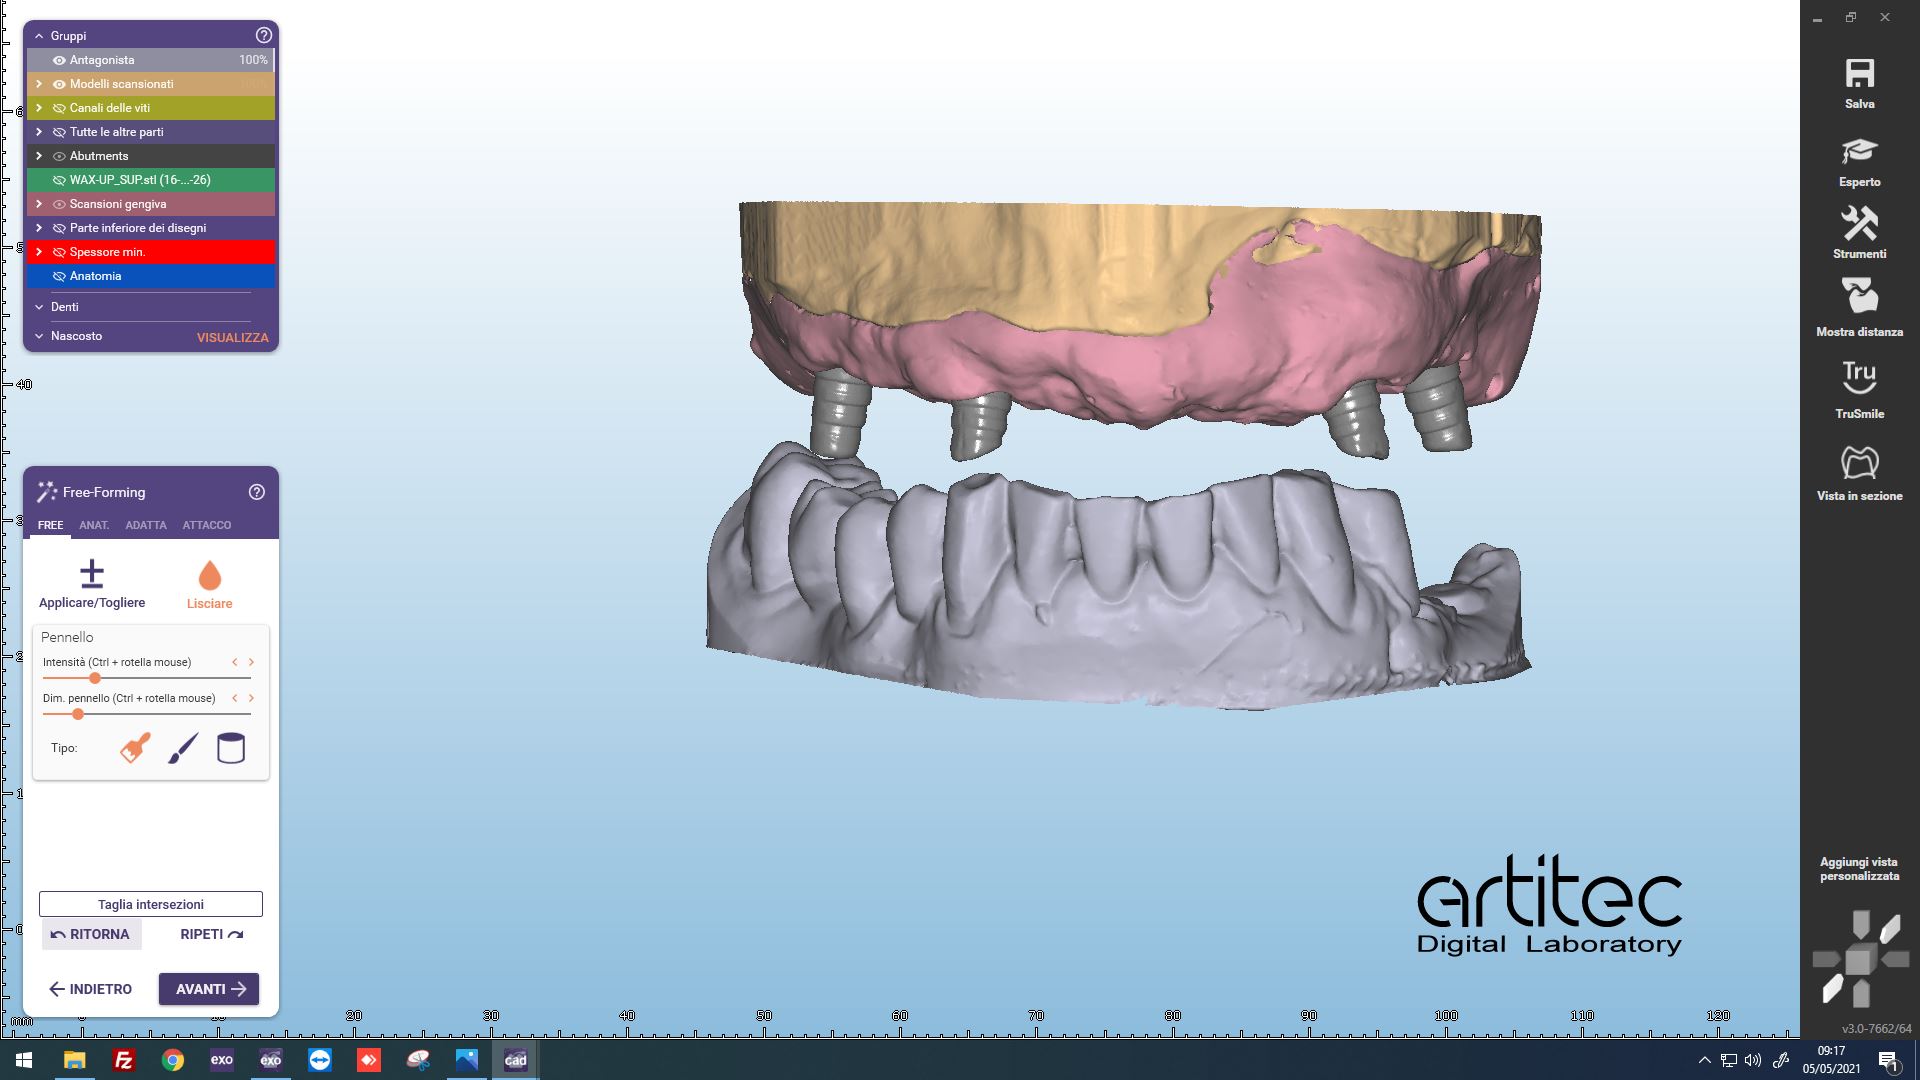

Fig. 5 Posizionamento anatomie dalle informazioni della scansione del provvisorio